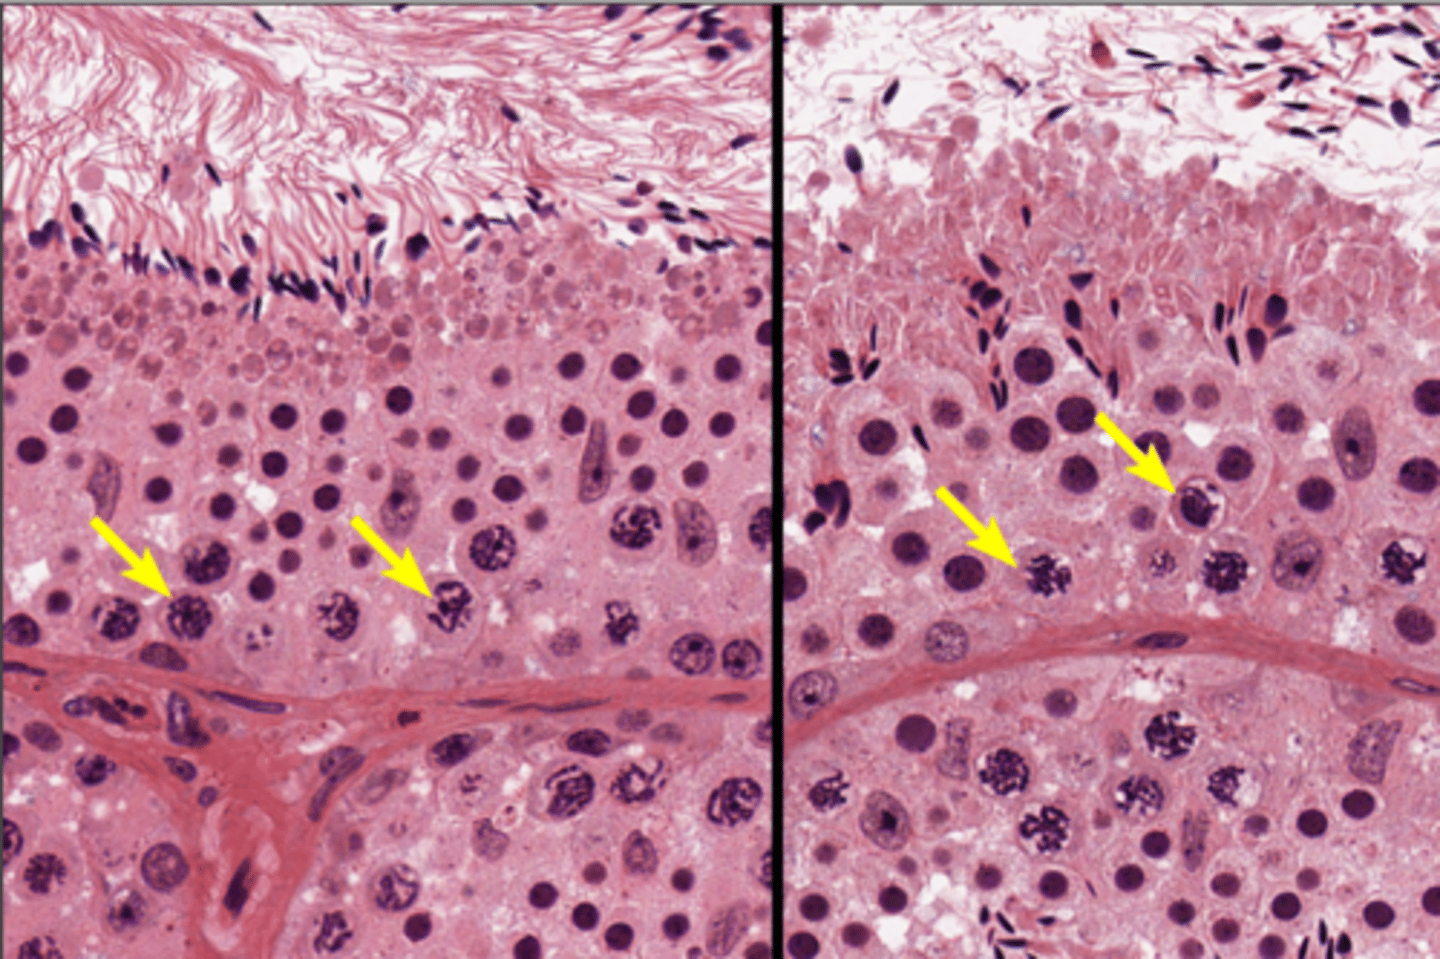

Seminiferous tubules

Seminiferous tubules

Seminiferous tubules

Spermatogenesis

Spermatogenesis

Spermatogonia

Primary spermatocyte

Spermatogonia

Spermatid (early)

Primary spermatocyte

Spermatid (late)

Spermatid (early)

Spermatozoon

Spermatid (late)

Spermatozoa